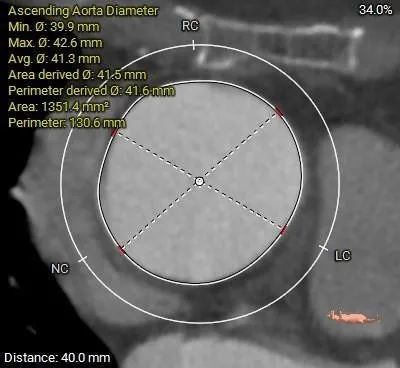

主动脉根部测量:

Type 0型二叶式主动脉瓣,瓣叶增厚,未见明显钙化,交界处未见明显融合

•瓦氏窦、窦管交界内径尚可,升主稍扩张(41.6mm)。